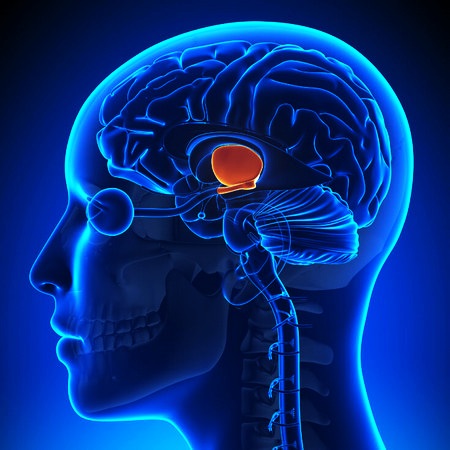

Промежуточный мозг в значительной степени закрыт конечным. Это – один из 4-х основных мозговых частей. Состоит из 3 пар структур – таламуса, гипоталамуса, эпиталамуса. Отдельные части ограничивают III желудочек. К гипоталамусу через воронку присоединен гипофиз.

Функция таламуса

Таламус составляет 80% от промежуточного мозга, является основой для боковых стенок желудочка. Ядра таламуса переориентируют сенсорную информацию от тела (спинного мозга) – боль, касание, визуальные или слуховые сигналы – в определенные мозговые области. Любая информация, направляющаяся в кору головного мозга, должна переориентироваться в таламусе – это ворота в мозговую кору. Информация в таламусе активно обрабатывается, меняется – он увеличивает или уменьшает сигналы, предназначенные для коры. Некоторые из ядер таламуса двигательные.